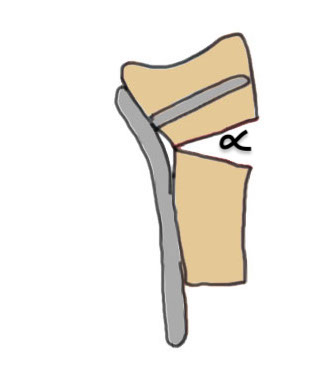

Dorsal tilt

- loss of flexion

+/- midcarpal instability - DISI / CIND without interosseous ligament disruption

Dorsal tilt / radial tilt / loss of inclination

Dorsal opening wedge

Dorsal opening wedge osteotomy

Advantage

Lengthens the distal radius

May be easier to correct in coronal and sagittal plane

Disadvantage

Dorsal approach / dorsal plate - extensor tendon issues

Technique

3 / 4 dorsal approach

- expose distal radius

- can use half pins to control distal fragment

- protect structures with homan retractors

- osteotomy with microsagittal saw

- correct radial articular surface in sagittal & coronal planes

- trapezoidal bi-cortical iliac crest autograft / synthetic graft

- dorsal locking plate